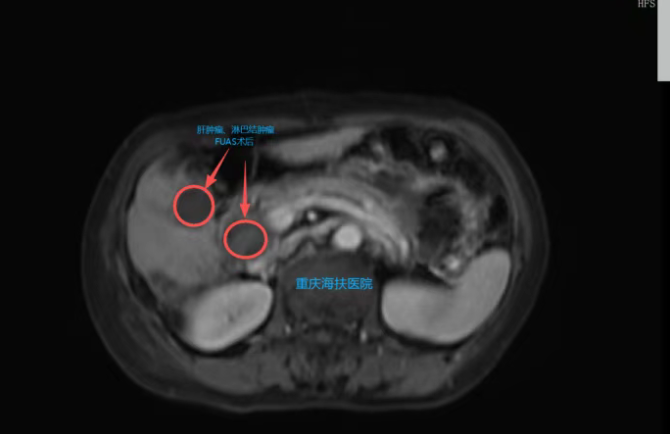

3月2日,张炼教授团队为患者实施全麻下聚焦超声消融治疗。一次性消融肝门淋巴结、肝脏病灶病变、门静脉癌栓,手术过程顺利。术后患者清醒,生命体征平稳,皮肤完好、无创口。

术后第1天,患者已进流食,无明显疼痛,仅轻微腹胀,复查指标整体平稳。复查MRI显示:消融区域肿瘤坏死明显,“黑洞”征清晰,提示病灶已被灭活。

此次治疗不仅灭活了肝内原发肿瘤,更成功处理了门静脉癌栓及转移淋巴结,充分体现了聚焦超声消融无创、精准、可一次性处理多处病灶的独特优势。